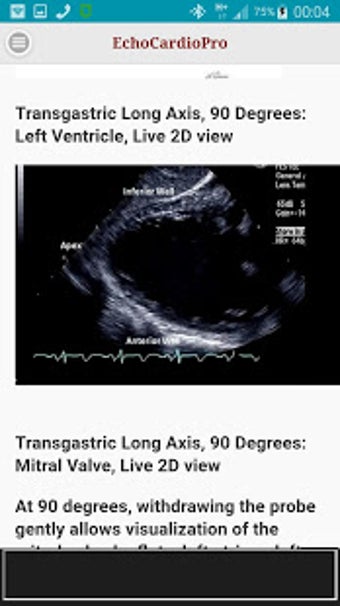

Aplikacja dostarcza kompleksowych informacji na temat echokardiografii przezklatkowej (TTE) i echokardiografii przełykowej (TEE) oraz ich odpowiednich korzyści w ocenie czynności skurczowej i rozkurczowej lewej i prawej komory, regionalnego ruchu ściany, wad zastawkowych serca i chorób osierdzia. Zawiera również szczegółowe informacje na temat różnych widoków, takich jak długoosiowy przysercowy, krótkoosiowy przysercowy, wierzchołkowy, podżebrowy, nadobojczykowy, śródprzełykowy, poprzezżołądkowy, głęboko poprzezżołądkowy i wysoko przełykowy.